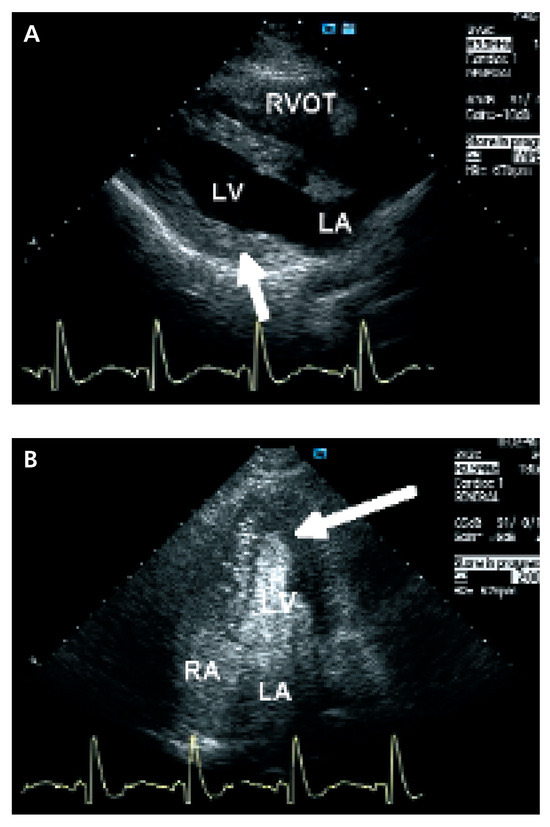

Update on Left Ventricular Hypertrophy

by Christina Attenhofer Jost

Detection and evaluation of left ventricular hypertrophy of unknown etiology by echocardiography is important in every cardiology practice. Causes of left ventricular hypertrophy include sarcomeric protein disorders (classical hypertrophic cardiomyopathy), metabolic disease (glycogen storage disease including LAMP2 deficiency, PRKAG2 mutations, Fabry disease), syndromic [...] Read more.

Detection and evaluation of left ventricular hypertrophy of unknown etiology by echocardiography is important in every cardiology practice. Causes of left ventricular hypertrophy include sarcomeric protein disorders (classical hypertrophic cardiomyopathy), metabolic disease (glycogen storage disease including LAMP2 deficiency, PRKAG2 mutations, Fabry disease), syndromic hypertrophic cardiomyopathy (Noonan’s syndrome, LEOPARD syndrome, etc.) and miscellaneous causes including systemic hypertension, amyloidosis, athlete’s heart and pheochromocytoma. Although there are several echocardiographic changes quite typical for some of the disorders, most changes are not 100% specific. ECG findings and symptoms provide important additional information. Genetic testing is increasingly important. Nowadays, a combination of ECG findings, symptoms, family history, genetic testing and findings of echocardiography provide the best means for differentiation of left ventricular hypertrophy. Full article

Figure 1